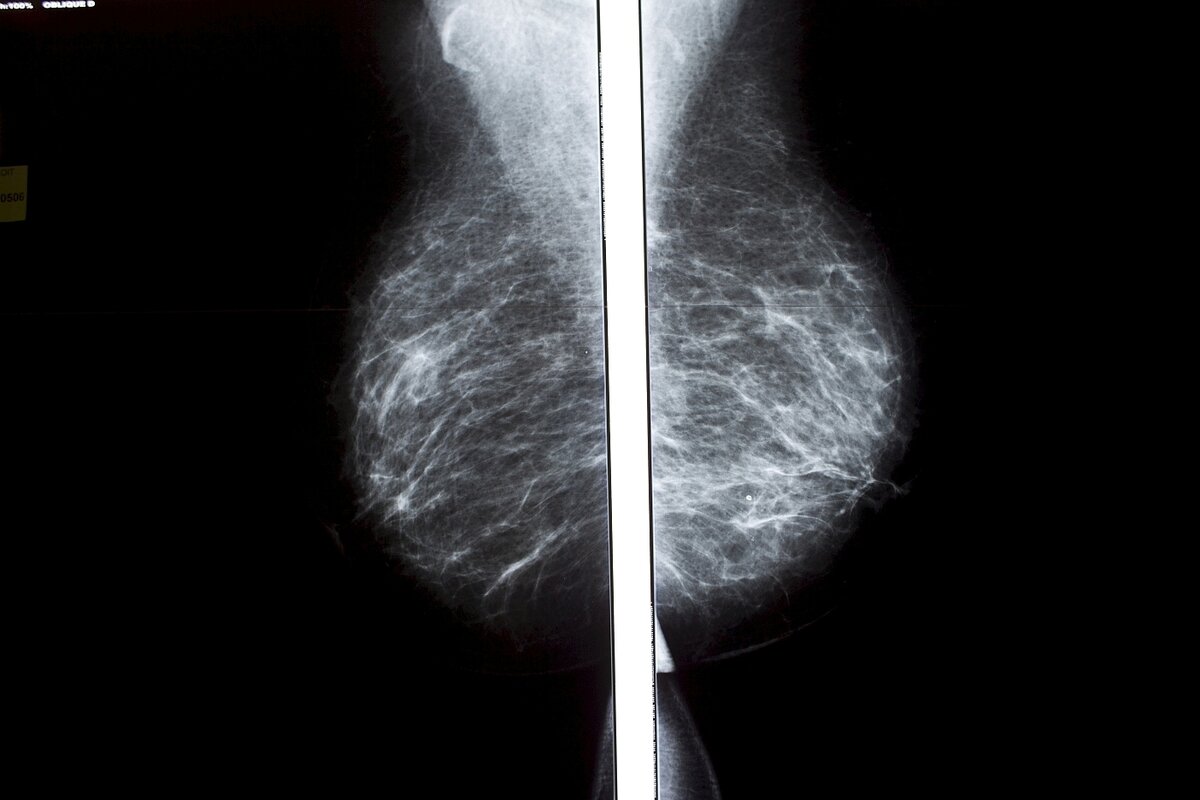

Mammographie einer weiblichen Brust: Wer den Befund nicht kennt, kann sich nicht behandeln lassen Foto: Marta Nascimento/REA/laif

Mehr als 2.000 Frauen wurden nach einer Brustkrebsvorsorgeuntersuchung nicht über das Ergebnis informiert, und das, obwohl die Mammographie „nicht eindeutig“ war oder „nicht klare Veränderungen“ zeigte. Jetzt wurde bekannt, dass es das Gesundheitssystem im südspanischen Andalusien monate-, ja in manchen Fällen jahrelang versäumte, die betroffenen Frauen zu benachrichtigen. Dabei hatte es erste Beschwerden über das Ausbleiben der Ergebnisse bereits 2023 gegeben.

Aus dem regionalen Gesundheitsministerium hieß es nun zuerst, die Frauen seien nicht benachrichtigt worden, um sie nicht „unnötig zu beunruhigen“. Die Fälle seien „grundsätzlich nicht schwerwiegend, sollten aber außerhalb der Vorsorge unter medizinischen Kriterien überwacht werden“, ergänzte eine Pressemitteilung der andalusischen Regierung. Nur: Wer den Befund nicht kennt, kann sich schlecht überwachen lassen.